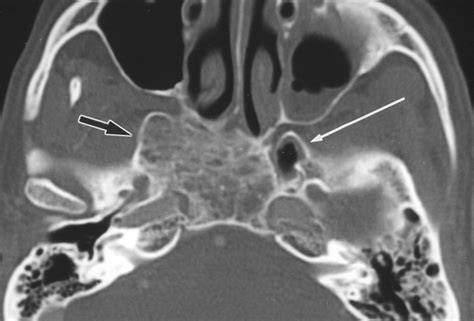

In modern medicine, diagnostic imaging is paramount for visualizing the Sphenoid Greater Wing. Plain radiographs are rarely sufficient for detailed evaluation due to the superimposition of other cranial structures. Consequently, Computed Tomography (CT) scans are the gold standard.

When reviewing CT scans of the skull base, radiologists look for:

1. Symmetry: Comparing the right and left wings to detect subtle displacements or fractures.

2. Foramen Integrity: Ensuring the foramen rotundum, ovale, and spinosum are not enlarged or eroded, which could indicate a tumor or chronic pressure.

3. Bone Density: Evaluating for signs of osteomyelitis, fibrous dysplasia, or metastatic lesions that might affect the sphenoid bone.